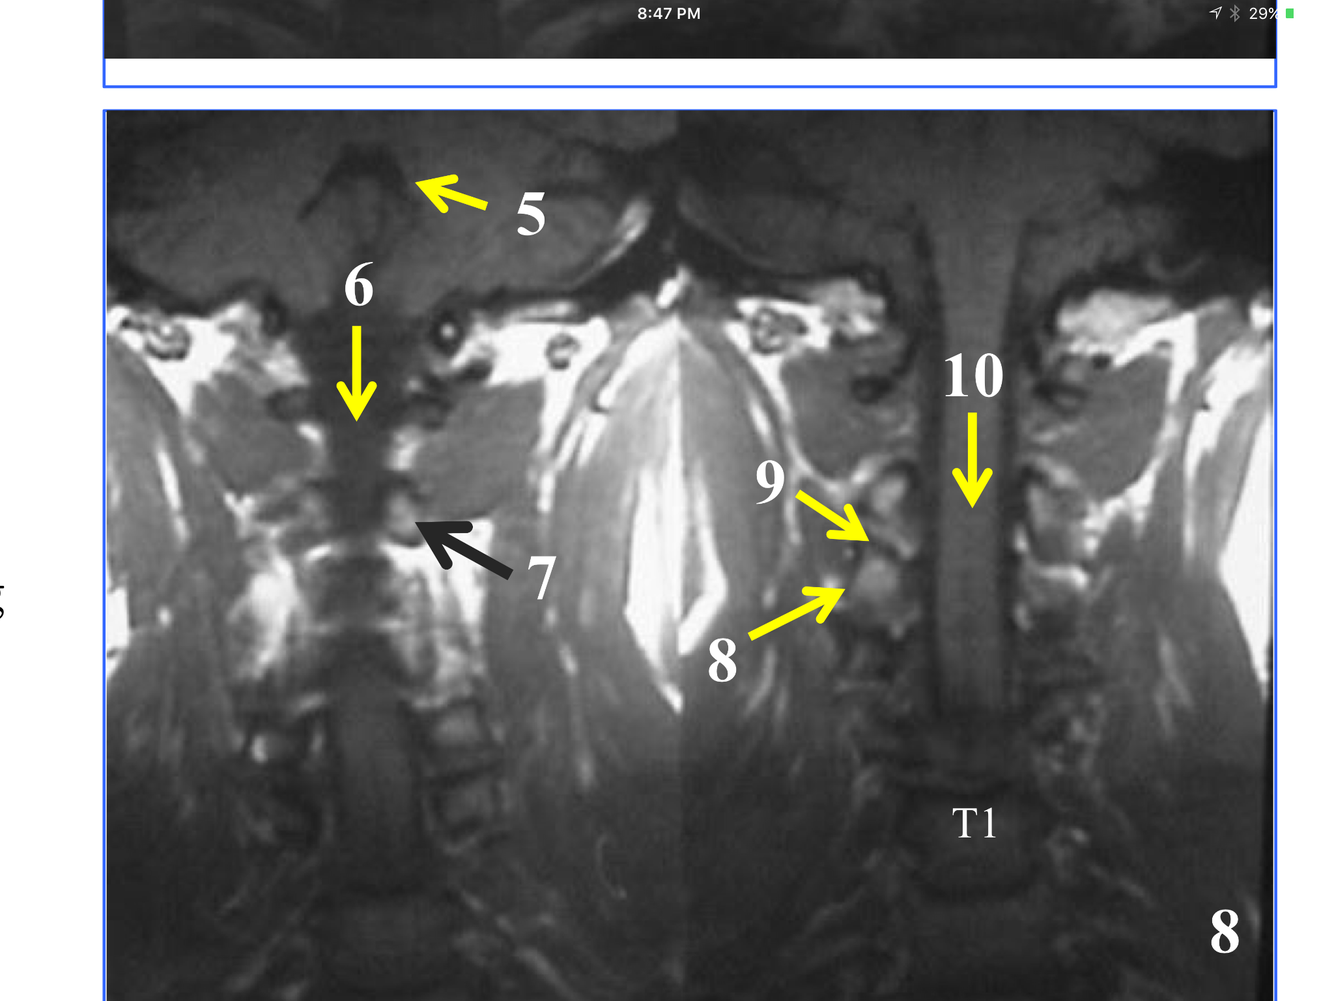

* Just superior to atlantoaxial joint

* The stack of inferior and superior articulating processes, and the zygapophyseal joints they form

*Comprised of the inferior and superior articulating processes, and the zygapophyseal joints they form

**10. Rt & Lt vertebral arteries**

*Although the transverse process is not seen, the tubercle articulates with the transverse costal facet on it.

*Immediately above the conus, which is at L1-L2

* Not seen in its entirety